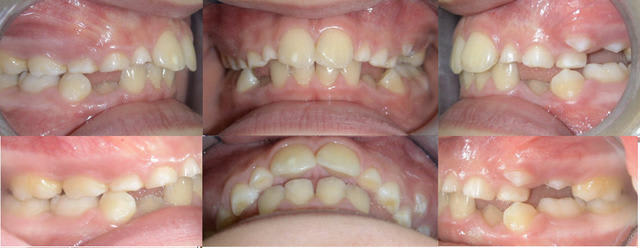

bon alors, sauf erreur on est face à un(e) brachy sévère, qui présente une agénésie des 2 dont la 23 est en train de faire son chemin, dévorant tout ce qui s'oppose à elle (II, III), la 13 a l'air de se plaire dans le palais; tout ceci dans un tableau de cl II 1.

Qu'est-ce-qu'on fait? pas évident avec ces deux documents. Comment est le sens transversal? Sinon, les deux possibilités sont: ouverture ou fermeture des espaces. Si on ferme( perte de 4 mm supplémentaires de longueur d'arcade), vu sa "brachytude", on va éviter d'extraire des prémo mandib, essayer de profiter du Leeway (est-il suffisant?)pour niveler et s'orienter vers la cl II thérap.

Si on ouvre, expansion maxillaire( la mandibule est verrouillée?), on laisse poindre la 23 avec la ptose de 62 63, et tu vas chercher la 13(vestibulaire, palatine?) va-t-elle rhizalyser 52 53 sur son passage, allons-nous devoir faire son chemin?

1- Les agenesies de 12/22: Quoi faire? ouvrir ou fermer?

Si on choisit la facilite, je metterais les 13-23 a la place des 12-22 manquantes, realise une coronoplastie des canines, regle la modeste DDM mandibulaire et je finis en classe II therapeutique en me disant une seule intevention pour degager la canine incluse suffit et ce n'est pas la peine d'envisager d'autre pour les implants plus tard.

Pour les plus courrageux il faut envisager la solution d'ouvrir en mettant en place une mecanique de classe II selon les objectifs fixes: de combien avancer le bas et de combien reculer le haut.

aux vues des photos, pas d'autre piste: le sens transversal est OK, petite rotation des molaires qui peut nous faire grapiller 2mm si on veut ouvrir les espaces + les quelques mm de la différence ((II +III)-3), si on veut implanter, on va devoir reculer les 6, non?

J'irais vers la mise en place de 13 et 23 à la place de 12 et 22.

1) extraction de 54,55,64,75,85(pour accélérer les définitives et commencer rapidement)

2) j'attends 15,14,24.

3) fixe multiattaches bi max

4) extraction de 52,53,62,63 et traction de 13 sur le MA.

Si 13 vient, coronoplastie de 13 et 23 et finition en cl 2 thérapeutique, avec contact incisif sup/inf.Je crains quand même la coudure de la racine de 13 lors de sa mise en place.

Je ne sens pas du tout la réouverture d'espaces sans extraire de PM au max; et comme il manque déja 12 et 22, j'ai pas envie.

Effectivement, il semble difficile de faire autrement que mettre les canines en position de latérales. Ton plan de traitement semble parfaitement correct, très classique.